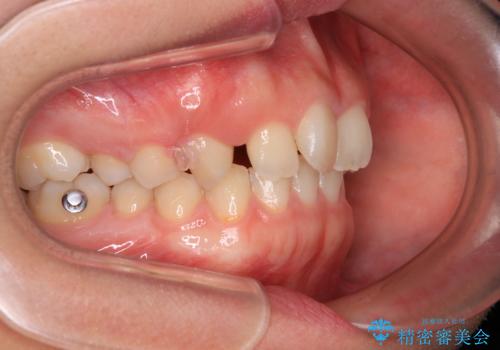

- 上の前歯が前方に飛び出していることを気にして来院された患者様です。

奥歯の咬み合わせをチェックすると、上顎歯列が相対的に前方に位置しているため、補助装置を用いて上顎歯列を確実に後方に移動させ、インビザラインで歯列を整えて行くこととしました。

インビザライン単体でも同様の結果が得られる可能性がありますが、万が一奥歯がうまく後方移動できなかった場合、リカバリーが非常に大変となるため、事前に補助装置を併用して確実に結果が得られるように工夫をしています。